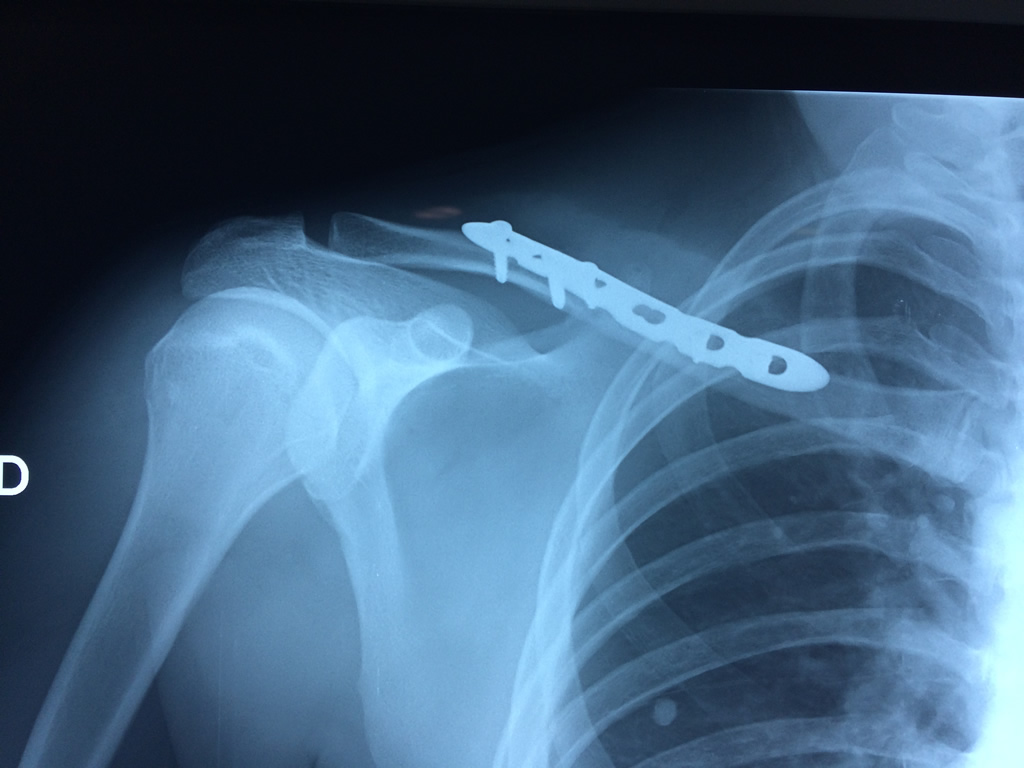

Cirugias en El Salvador - Clavícula

La clavícula es un hueso largo, con forma de "S" itálica, situado en la parte anterosuperior del tórax. Junto con la escápula forman la cintura escapular. Se puede palpar por toda su longitud y se extiende del esternón al acromion de la escápula, siguiendo una dirección oblicua lateral y posterior.

Se considera el único medio de unión entre el miembro superior y el tórax. A pesar de su aspecto, similar al de un hueso largo, posee una estructura semejante a la de un hueso plano, ya que carece de epífisis y de diáfisis, lo que la harían entrar dentro de la clasificación de hueso largo. Carece de un canal medular propiamente dicho.